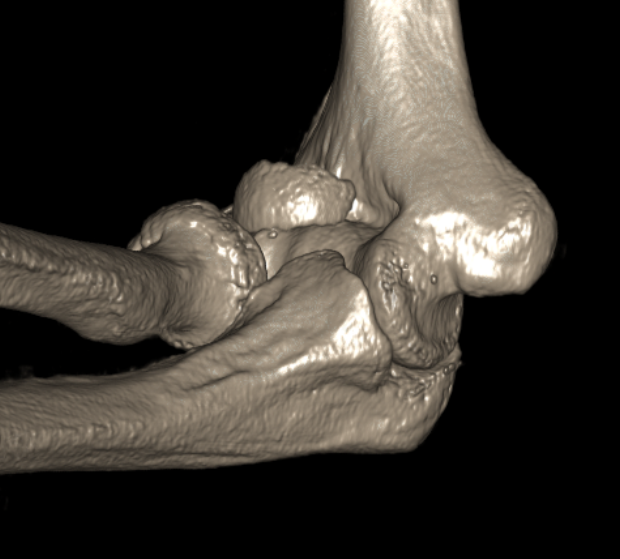

Knee

ApproachesPosterior approach knee